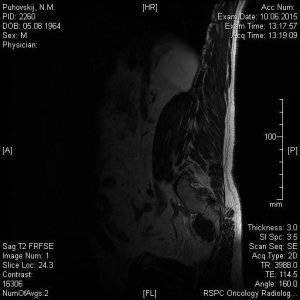

Сегодня сделали МРТ поясничного отдела позвоночника моему отцу. Результат записан на СD диск с множеством фото, заключение, соответственно, прилагается. Но для полной уверенности хотелось бы подтверждения иного специалиста. Основные симптомы: острые и постоянные боли в пояснице, периодически "отказывают" ноги (приходится постоянно менять свое положение-присесть, выгнуться, нагнуться, пройтись и т.п). Не маловажный факт, что около 5 лет назад с идентичными симптомами у папы обнаружили грыжу и удалили ее. Опыт имеется, а страх все равно присудствует. Помогите пожалуйста.

image.jpg32 КБ · Просмотры: 678

image.jpg32 КБ · Просмотры: 678 -